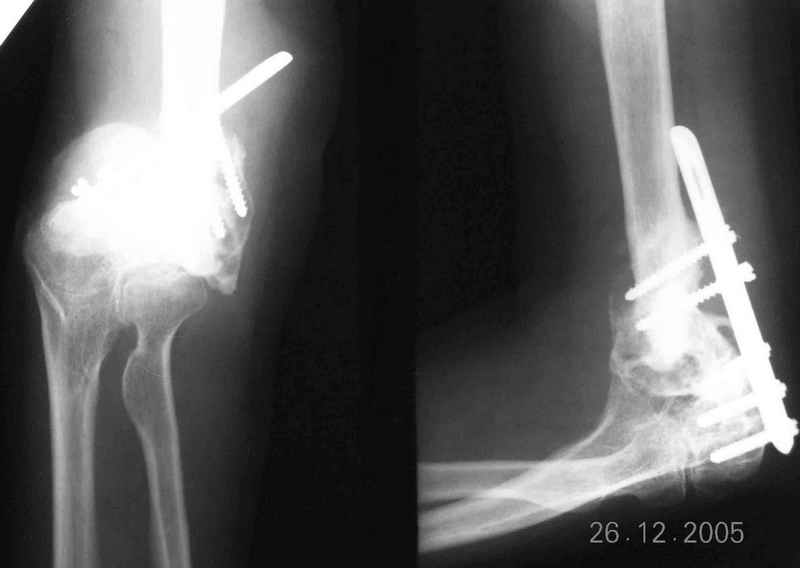

The recent x rays show established Non union with poor quality bone in the distal fragement. The joint is also appearing degenerate. In view of the multiple failed reconstructive surgeries, an Elbow replacement would seem reasonable.

However it would have to be a fully constrained one as there would be missing bone stock.

Уважаемый Ильдар, в ноябре 2005 г. мы оперировали практически полностью идентичную ситуацию у больного с гемофилией, поставили модифицированный

эндопротез локтевого сустава типа Сиваша с хорошим результатом. На заводе-производителе (в нашем случае - завод ЦИТО, но есть еще ООО